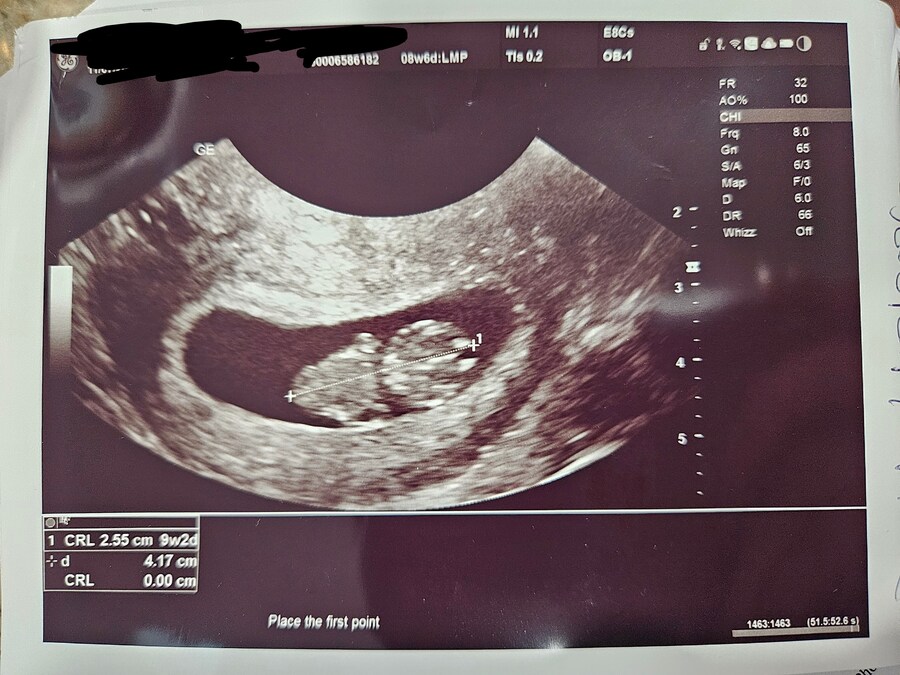

지금 약 9주이고 오늘 병원가서 초음파 보고 옴요. (미국은 8주 이하 초음파 안함)

크기 정상. 심박동 정상이라 캅니다.

옆으로 누운 치킨 모양.